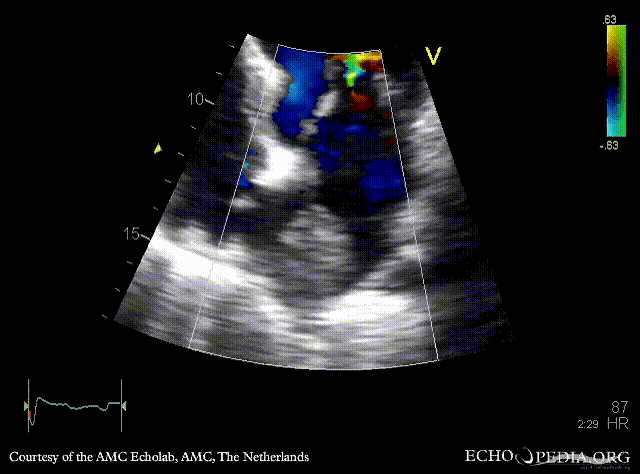

Tumor growing into the left atrium

Courtesy of: AMC Echolab, AMC, The Netherlands

A4CH: tumor growing from pulmonary vein into the left atrium in patient with lung carcinoma A4CH, zoom